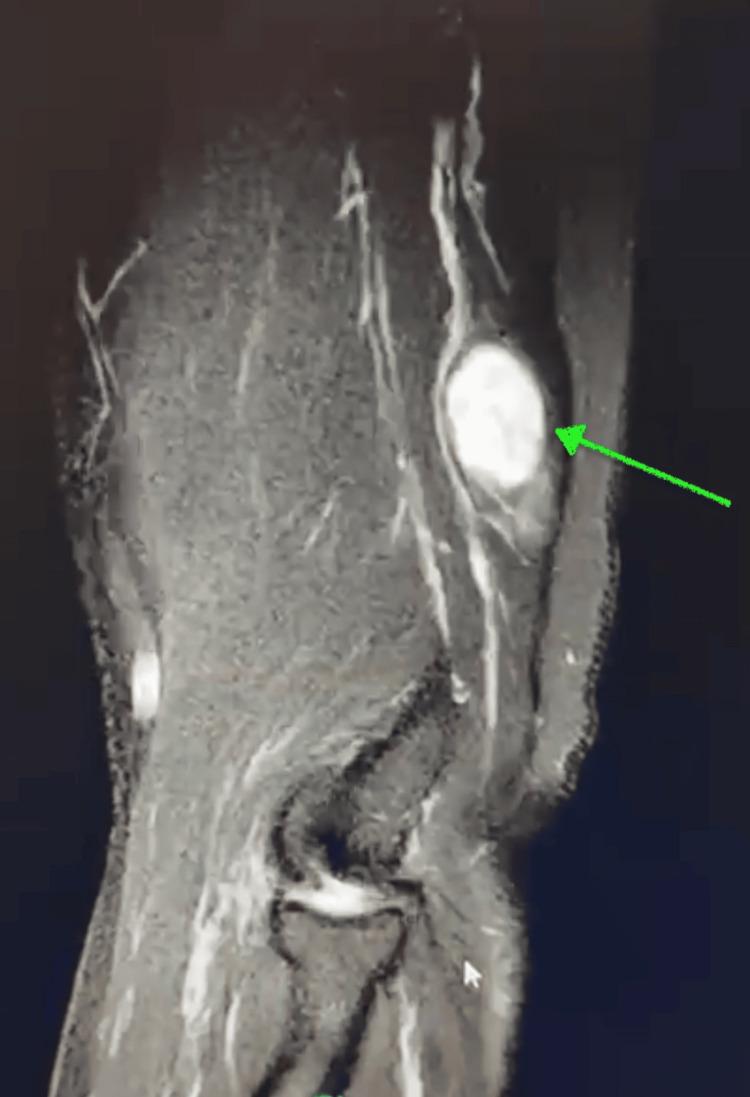

Schwannomas are uncommon, mostly benign nerve sheath tumors that typically present as painless or intermittently painful lumps. They are most commonly found on the flexor surfaces of the body, with occurrence in the radial nerve being exceptionally rare. We present the case of a 55-year-old male with a five-month history of a progressively enlarging, mobile mass on the posterior aspect of the right arm. The patient presented with a transient, "shock-like pain" that failed to respond to conservative management. Imaging confirmed a peripheral nerve schwannoma located deep in the triceps posterior fascia along the lateral head of the triceps within the radial nerve. Due to persistent symptoms and failure of conservative treatment, surgical excision of the neural tumor was recommended. This case highlights the clinical presentation and surgical management of a rare radial nerve schwannoma.

神经鞘瘤并不常见,大多为良性神经鞘膜肿瘤,通常表现为无痛或间歇性疼痛的肿块。它们最常见于身体的屈侧表面,在桡神经中出现极为罕见。我们报告一例55岁男性患者,其右臂后侧有一个进行性增大的可移动肿块,病史长达五个月。患者出现短暂的“电击样疼痛”,保守治疗无效。影像学检查证实为外周神经鞘瘤,位于桡神经内肱三头肌外侧头沿肱三头肌后筋膜深处。由于症状持续且保守治疗失败,建议手术切除神经肿瘤。本病例突出了罕见的桡神经鞘瘤的临床表现及手术治疗。